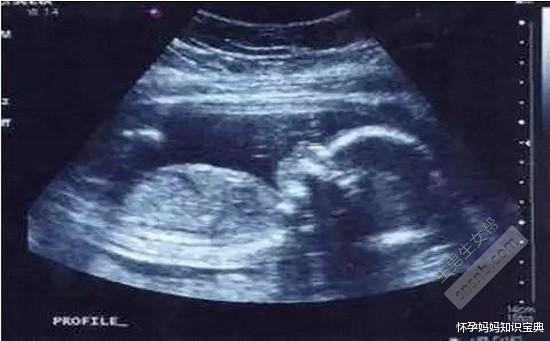

孕男宝生殖彩超图,男宝彩超图片男女

男宝彩超图片男女

男宝b超图典型的

最明显的男宝b超图

男宝b超图特点

男宝彩超图片

男宝b超图片

男宝b超